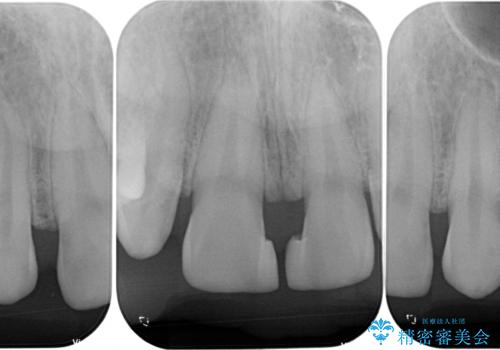

- 歯の欠損による前歯のすきっ歯を気にして来院された患者様です。

矯正治療かオールセラミックか、治療の選択がありましたが、熟考の末オールセラミッククラウンにて補綴することとしました。